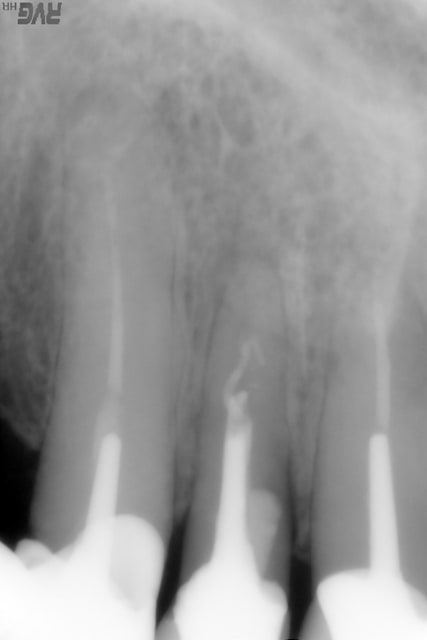

par ailleurs, voici ce qui se passe aussi quand on met du TCP et que l'on attend 6 mois; j'ai perdu un implant en janvier 2007 sur une infection post op à 3 semaines avec une couverture par birodogyl, j'ai remplacé l'implant fin septembre, l'os est magnifique, bien vascularisé, et je pose les ccm la semaine prochaine :-)

si si, les voici

1 implant 02 07 nxo7lr - Eugenol

2 pose tcp 02 07 wxcjq2 - Eugenol

3 tcp 08 2007 wx4aom - Eugenol

4 implant 28 9 07 iqohwd - Eugenol